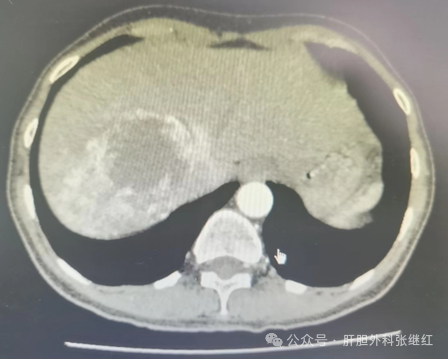

肝血管瘤主要是胚胎发育中血管发育异常所致的血管畸形,是最常见的肝良性肿瘤之一。大多数肝血管瘤生长缓慢,甚至到了一定程度便停止生长,临床上一般在单个直径5Cm以下者,只要不再增长,一般对身体不会构成危害。目前未发现对肝血管有疗效的药物。既往观点认为:肿瘤直径<5cm者,不需手术治疗,定期复查,随诊即可;肿瘤直径510cm者,可考虑手术治疗;肿瘤直径>10cm者,一般行手术治疗。然而,肝血管瘤的治疗,特别是手术治疗的指征问题,一直存在较大争议。为了尽可能规范肝血管瘤的诊治,2019年国际肝胆胰协会中国分会制定了《肝血管瘤诊断和治疗多学科专家共识(2019版)》(下文简称共识),将肝血管瘤分为三级三型,并提出了各级各型的治疗原则与方法。

根据肝血管瘤瘤体的大小分为小血管瘤(肿瘤直径<5cm),大血管瘤(肿瘤直径510cm)和巨大肝血管瘤(肿瘤直径10cm以上)三级。根据肝血管瘤的数量将其分为3型,各型又根据瘤体大小或肿瘤直径之和或体积之和分为23个亚型,即:I型为单发肝血管瘤,肿瘤直径<5cm的为Ia型,肿瘤直径510cmIb型,肿瘤直径10cm以上为Ic型;II型为多发肝血管瘤,瘤体2-5个,肿瘤直径之和<10cmIIa型,肿瘤直径之和1020cmIb型,肿瘤直径之和20cm以上为IIc型;III型为弥漫型肝血管瘤,瘤体超过5个,弥漫性分布,瘤体体积之和小于肝体积的50%IIIa型,瘤体体积之和超过肝体积50%IIIb型。

肝血管瘤是否需要治疗取决于有无危险因素的存在。危险因素是指肝血管瘤伴有症状、严重并发症、迅速增长或不除外恶变等危及患者健康或可能危及患者健康的因素。对于不伴危险因素的IIIIII型肝血管瘤病人,无论肿瘤大小、位置,原则上以随访观察为主,建议半年或1年复查一次;伴有危险因素的肝血管瘤才需要酌情治疗。对于三级肝血管瘤,一般来说,小血管瘤无症状,不危害身体,不需任何治疗,随访观察即可;大血管瘤和巨大血管瘤伴有危险因素才需酌情治疗。